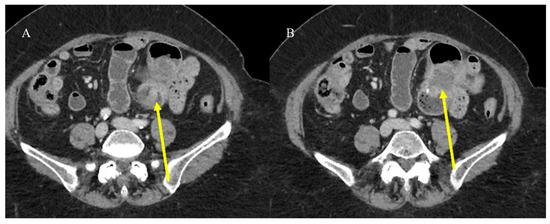

- Tran, C.G.; Sherman, S.K.; Howe, J.R. Small bowel neuroendocrine tumors. Curr. Probl. Surg. 2020, 57, 100823. [Google Scholar] [CrossRef] [PubMed]

- Ganeshan, D.; Bhosale, P.; Yang, T.; Kundra, V. Imaging features of carcinoid tumors of the gastrointestinal tract. AJR Am. J. Roentgenol. 2013, 201, 773–786. [Google Scholar] [CrossRef]

- Gupta, A.; Lubner, M.G.; Menias, C.O.; Mellnick, V.M.; Elsayes, K.M.; Pickhardt, P.J. Multimodality imaging of ileal neuroendocrine (carcinoid) tumor. AJR Am. J. Roentgenol. 2019, 213, 45–53. [Google Scholar] [CrossRef]

- Gangi, A.; Siegel, E.; Barmparas, G.; Lo, S.; Jamil, L.H.; Hendifar, A.; Nissen, N.N.; Wolin, E.M.; Amersi, F. Multifocality in small bowel neuroendocrine tumors. J. Gastrointest. Surg. 2018, 22, 303–309. [Google Scholar] [CrossRef]